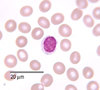

What are eosinophil and when are they normally found?

- Cells with a double lobed nucleus with red granules.

- Found scattered throughout the tissues

- Attack large parasites such as worms

- Present in high numbers in some immune responses:

- bronchi of asthmatics

- Hodgkins lymphoma